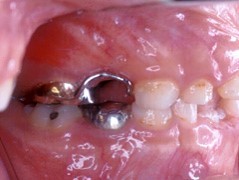

在混合齒列期中,維持將來永久牙長出時所需要的空間,也是乳牙存在的重要性之一。不幸的是,往往有許多的原因使得乳牙提早脫落,造成乳牙維持空間的功用消失。而使乳牙提早脫落的原因通常有:因為蛀牙太大,導致乳牙需要被拔除;因為意外創傷而使乳牙提早脫落;因為永久牙太大或異位生長而造成旁邊乳牙提早脫落;治療失敗的乳牙,需要提早被拔除…等等。

一旦乳牙提早不存在時,我們若沒有及時做好適當處理的話,這些寶貴的空間就會因後牙的前傾移動,而造成萌牙空間的消失;於是將來小孩齒列提早掉落後,需要採取何種適當的防範措施,使得將來牙齒萌長空間不足的機會大大地減低,或者縮短將來需要做矯正治療的過程及時間,甚至完全免除小孩牙齒矯正的需要?空間維持器就是我們的答案了。